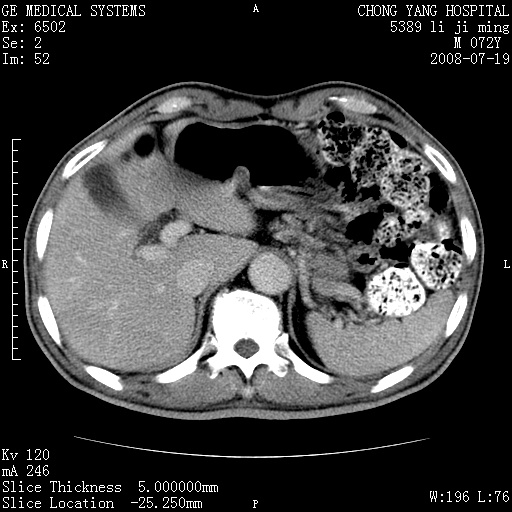

以下是引用zjzjr在2008-7-19 20:57:00的发言:[br]胰头增大,边缘模糊,周围可见渗出影,右侧肾前筋膜增厚.支持胰腺炎.

以下是引用yangyudong333在2008-7-20 6:56:00的发言:[br]胰腺增大尤以胰头明显,边缘模糊,周围可见渗出影,右侧肾前筋膜增厚,肠管於涨.支持胰腺炎

以下是引用不学无术在2008-7-19 23:15:00的发言:[br]胰腺增大尤以胰头明显,边缘模糊,周围可见渗出影,右侧肾前筋膜增厚,肠管於涨.支持胰腺炎